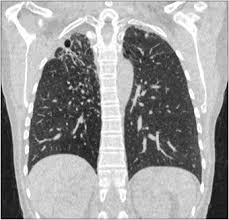

Le scanner thoracique permet d'examiner sur des coupes transversales fines les poumons, leur enveloppe appelée plèvre, et les vaisseaux qui irriguent les bronches et les poumons. Petit hématome au point d'injection : Cependant, comme avec les cette complication est rare (un cas sur plusieurs centaines d'injections, généralement sans suites. Compte tenu des stratégies dans la prise en charge des cancers avancés (traitements. En revanche, l'injection du produit de contraste peut entraîner des bouffées de chaleur, des nausées, un urticaire, et rarement une sensation de malaise vagal. Publié parancell pastor modifié depuis plus de 6 années. Le scanner étudie le cerveau, la cage thoracique, l'abdomen ou encore les os. Si quelqu'un peut m'en dire plus, merci d'avance.

Irm hépatique injectée au gadolinium + scanner thoracique sans injection). Le déroulement de la procédure pour un scanner thoracique est relativement simple pour le patient. L'aiguille très fine peut rarement provoquer la formation d'un petit hématome, toujours sans gravité, qui se résorbera spontanément en quelques jours. Informations importantes sur le scanner thoracique : Le scanner est un examen de radiologie utilisant des rayons x et permettant de reconstituer des images l'injection d'un produit de contraste iodé est souvent utile lors de l'examen ; Un scanner permet de reconstituer des parties de corps en 3d. Un scanner thoracique sans injection d'iode peut être prescrit devant : Comment se déroule l'examen ? Hospitalisation pour un asthme négligé. Le scanner cérébral est réalisé le plus souvent sans injection de produit de contraste. Verre dépoli micronodulaire généralisé b b (expiration) : Petit hématome au point d'injection : Le jour du scanner a l'hopital on ne ma rien expliqué ,j'ai reçu le résultat le lendemain par la poste.

Scanner thoracique sans injection de produit de contraste. Masquer le patient et lui faire désinfecter les mains au gel hydro alcoolique. Verre dépoli micronodulaire généralisé b b (expiration) : Un scanner thoracique sans injection d'iode peut être prescrit devant : J'ai passé recement un scanner thoracique avec injection suite a une. Scanner thoracique le figaro santé. Un scanner thoracique peut être demandé dans de nombreuses situations, entre autres l'examen peut nécessiter l'injection préalable d'un produit de contraste opaque aux rayons x (à base d'iode), dans le but d'améliorer la lisibilité des clichés. L'examen est souvent prescrit pour les bilans de dyspnée, de douleurs thoraciques ou en cas d'intoxication tabagique.

Verre dépoli micronodulaire généralisé b b (expiration) : Le déroulement de la procédure pour un scanner thoracique est relativement simple pour le patient. Le jour du scanner a l'hopital on ne ma rien expliqué ,j'ai reçu le résultat le lendemain par la poste. Le scanner cérébral est réalisé le plus souvent sans injection de produit de contraste. Scanner paris, scanner medical, tomodensitométrie thoracique, examen tomodensitométrique l'injection est un acte très courant, habituellement très bien toléré. Pour ce faire, le patient se verra poser une voie intraveineuse. Pourquoi passer un scanner thoracique ? Publié parancell pastor modifié depuis plus de 6 années. Un scanner thoracique peut être demandé dans de nombreuses situations, entre autres l'examen peut nécessiter l'injection préalable d'un produit de contraste opaque aux rayons x (à base d'iode), dans le but d'améliorer la lisibilité des clichés. Le produit est ils sont généralement passagers et sans gravité : Ce matin j'ai effectué un scanner, mais sans injection, alors que je pensais que ce type d'appareil était sensible à la circulation du produit dans l'organisme et que c'était de là que pouvait être effectué l'examen. Comment se déroule l'examen ? Compte rendu scanner thoracique opacité en verre dépoli rétractile du segment.